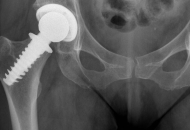

Spiron® / CoxaFit® – OP